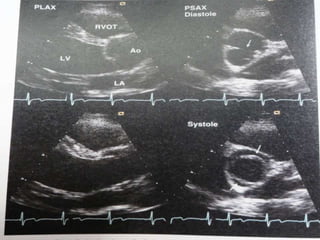

2D Echo-Long axis view

Diastole Systole

2D Echo-Short axis view

Y or inverted Mercedes-Benz sign